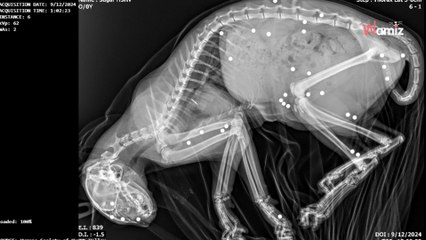

« C'est un miraculé »: après avoir reçu quarante balles de plomb dans la tête, ce chien s'en est sorti vivant